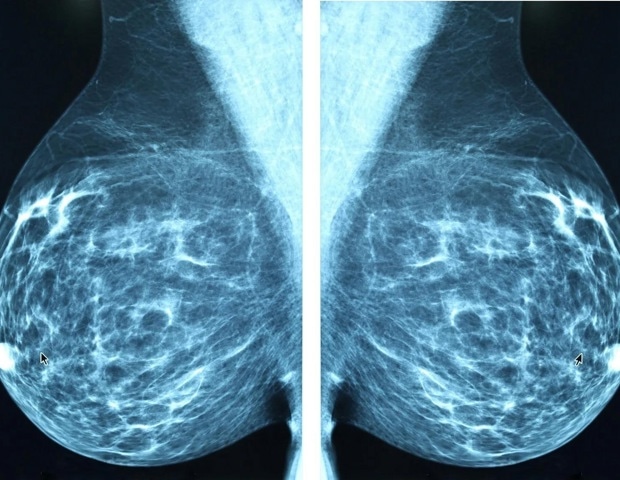

Une nouvelle molécule développée par des chercheurs de l’Oregon Health & Science University offre une voie prometteuse pour traiter les cas incurables de cancer du sein triple négatif – une forme de cancer notoirement agressive et dépourvue de traitements efficaces.

Dans une étude publiée aujourd’hui dans la revue Rapports cellulaires Médecineles chercheurs décrivent l’effet d’une molécule connue sous le nom de SU212 pour inhiber une enzyme essentielle à la progression du cancer. La recherche a été menée sur un modèle de souris humanisée.

Le cancer du sein triple négatif représente jusqu’à 15 % de tous les cancers du sein.

À l’aide d’un modèle murin humanisé, les chercheurs ont testé la molécule SU212 contre le cancer du sein triple négatif. La molécule se lie à une enzyme appelée énolase 1, ou ENO1, qui régule les niveaux de glucose dans les cellules humaines et est surexprimée dans les cellules cancéreuses.

La molécule a induit la dégradation de l’enzyme et a finalement supprimé la croissance tumorale et métastase chez les souris.